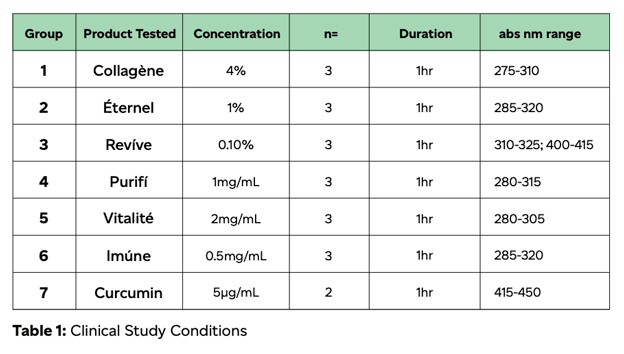

Cellular absorption and bioavailability was determined by use of a Caco-2 permeability assay using 0.4 μM pore size in a 12-well plate format. Filter was pre-incubated with media for 30 minutes before seeding the cells. 100 μL apical, 600 μL basal. 3X10^5 cells were plated per insert. Media volume was set to 0.5 mL apical and 1.6 mL basal. Media was replaced every 2-3 days until tight junction formation. Products were tested at the concentrations, durations, and then quantified at the absorption ranges shown in Table 1 below.